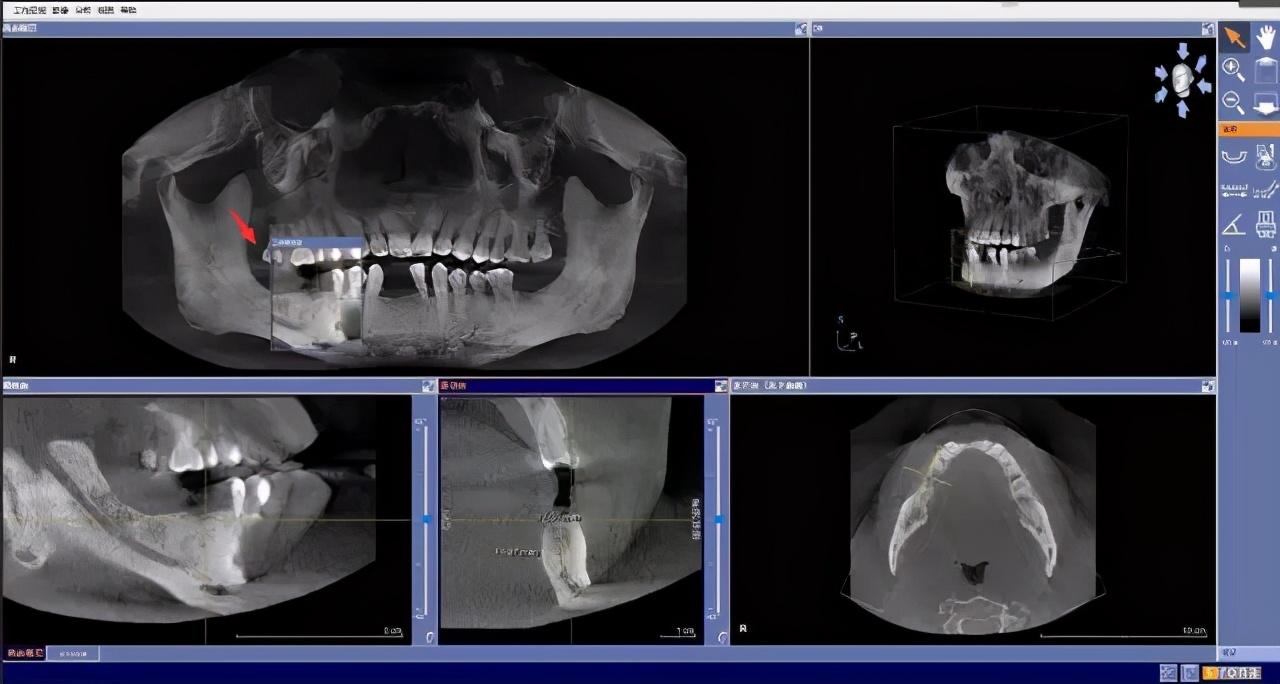

step1

先要做一個(gè)口腔全景片、頜骨CT等

醫(yī)生根據(jù)機(jī)器成像查看口腔的具體情況,

是否有炎癥、牙槽骨的密度、吸收狀況

以及鄰牙組織、牙體組織等。

注明:此數(shù)據(jù)僅作模擬,不是確切種植數(shù)據(jù)。

如果僅靠雙眼大致估測(cè)口內(nèi)數(shù)據(jù),是無(wú)法得到的高度、寬度的,也無(wú)法確認(rèn)骨頭吸收多少,是否需要植入骨粉。

對(duì)后期手術(shù)有一定的影響。

通過(guò)全景片可以“解剖”牙齒測(cè)量,適宜的種植角度也可確定,健康有保障。